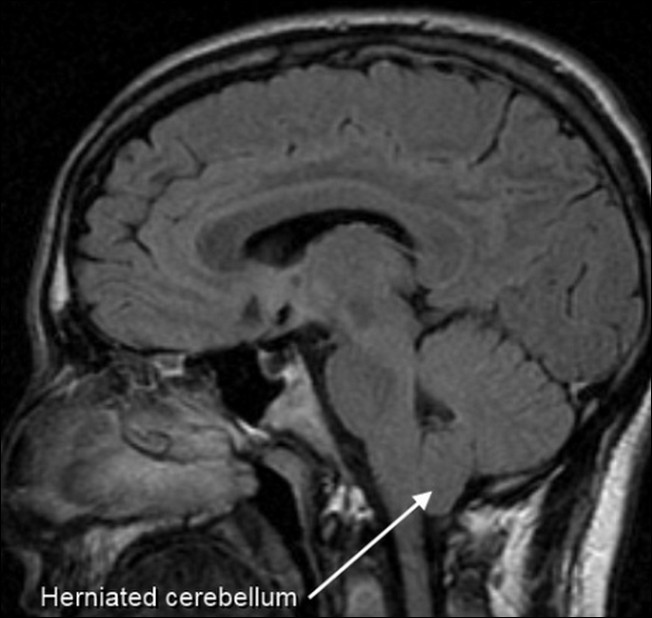

8. Arnold Syndrome

Sindrom ini menyebabkan seseorang kehilangan tulang selangka dan bisa menular secara genetik... seseorang dengan kelainan ini bisa membuat bahu yang satu menyentuh bahu lainnya